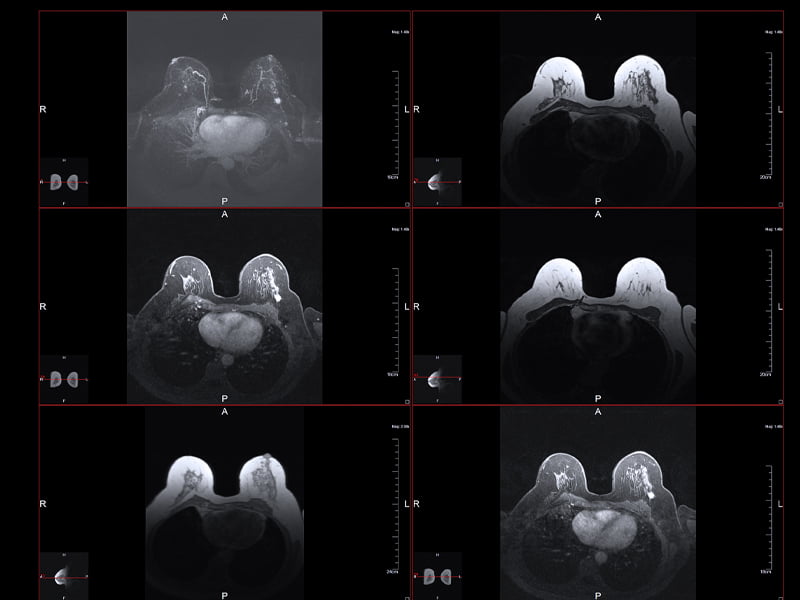

Breast cancer is diagnosed through various methods, including mammograms, ultrasounds, biopsies, and imaging tests. Treatment options depend on the stage of the cancer, its type, and the individual’s overall health. Common treatments include: